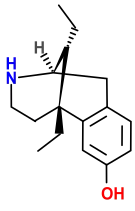

Morphinans

Morphinan series

- 3-Hydroxymorphinan

- 4-Chlorophenylpyridomorphinan

- Cyclorphan

- Levargorphan

- Levorphanol

- Levophenacylmorphan

- Levomethorphan

- Methorphan (racemethorphan)

- Morphanol (racemorphanol)

- Norlevorphanol

- N-Methylmorphinan

- Oxilorphan

- Phenomorphan

- Proxorphan

- Ro4-1539

- Stephodeline Xorphanol

Structures

| Other morphinans | ||||

|---|---|---|---|---|

4-chlorophenylpyridomorphinan 4-chlorophenylpyridomorphinan |

Cyclorphan Cyclorphan |

Dextrallorphan Dextrallorphan |

Levargorphan Levargorphan |

Levophenacylmorphan Levophenacylmorphan |

Levomethorphan Levomethorphan |

Norlevorphanol Norlevorphanol |

N-Methylmorphinan N-Methylmorphinan |

Oxilorphan Oxilorphan |

Phenomorphan Phenomorphan |

Dextromethorphan Dextromethorphan  levomethorphan levomethorphan |

Morphanol Morphanol |

Ro4-1539 Ro4-1539 |

Stephodeline Stephodeline |

Xorphanol Xorphanol |